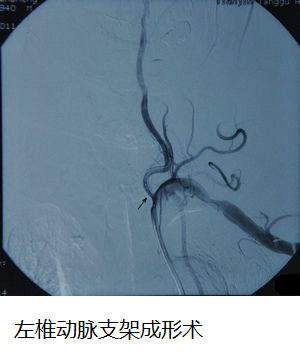

患者及其家属在详细了解手术指征及可能存在的风险后签字同意做手术。在完善各种术前准备后行全脑血管造影术,右侧椎动及左椎动脉支架成形术。手术顺利,造影见支架成形良好,原狭窄基本纠正。术后患者无头痛头晕症状,无发热,无恶心呕吐症状,生命征平稳,恢复良好,目前该患者在进一步康复中。